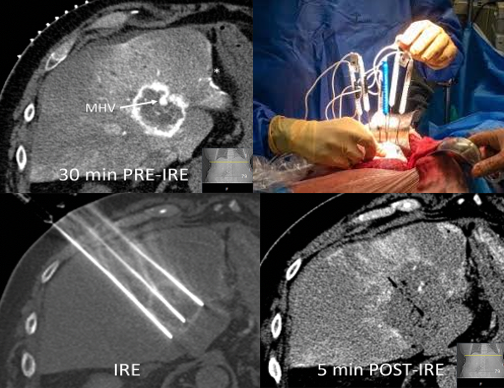

Habitualmente en la práctica clínica se usa un campo eléctrico que varía entre 1.000-1.500V/cm. El pulso eléctrico debe ser aplicado exactamente 50μs después de la onda R para que coincida con el periodo refractario absoluto del miocardio en el ciclo cardiaco. Es necesario que los pacientes se encuentren bajo anestesia general y bajo efecto de relajantes de la placa muscular tales como el rocuronio para evitar las contracciones musculares que desencadenan los pulsos. (Fig. 4).

Figura 4: imagen de TAC, técnica y resultado de la electroporación